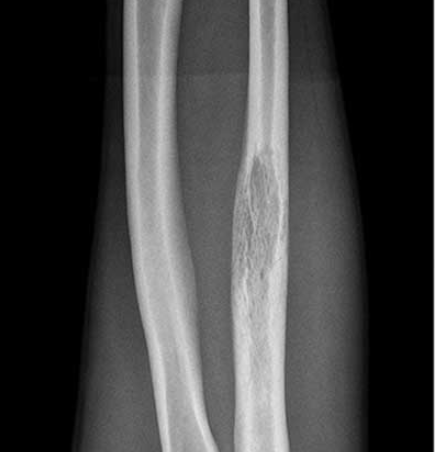

Tibia and fibular

Tibia: direct medial approach directly onto bone

Proximal Tibial Lytic Epiphyseal Lesion XrayTibia biopsy 1

Tibial Shaft LesionTibia biopsy 2